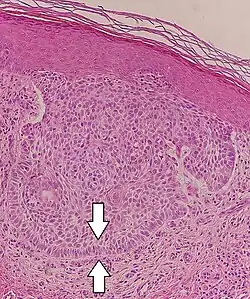

Nodular basal-cell carcinoma

.jpg)

Nodular basal-cell carcinoma (also known as "classic basal-cell carcinoma") accounts for 50% of all BCC.[29] It most commonly occurs on the sun-exposed areas of the head and neck.[30]: 748 [31]: 646 Histopathology shows aggregates of basaloid cells with well-defined borders, showing a peripheral palisading of cells and one or more typical clefts.[29] Such clefts are caused by shrinkage of mucin during tissue fixation and staining.[32] Central necrosis with eosinophilic, granular features may also be present, as well as mucin. The heavy aggregates of mucin determine a cystic structure. Calcification may also be present, especially in long-standing lesions.[29] Mitotic activity is usually not so evident, but a high mitotic rate may be present in more aggressive lesions.[29] Adenoidal BCC can be classified as a variant of NBCC, characterized by basaloid cells with a reticulated configuration extending into the dermis.[29]

Cleft.